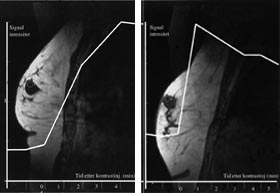

Tumordiagnostikk hos pasienter som har silikonimplantater som ledd i en brystrekonstruksjon eller av kosmetiske grunner, er vanskelig med mammografi. Dersom heller ikke ultralydundersøkelse, eventuelt med ultralydveiledet aspirasjonscytologi, gir avklaring, kan det hos denne pasientgruppen være indikasjon for MR-undersøkelse ved tumormistanke. Ved vevsprøvetaking fra tumorsuspekte områder nær implantatet kan det være en risiko for å punktere silikonprotesen. Våre egne erfaringer viser at MR-veiledet biopsi eller finnålsaspirasjon av tumorsuspekte områder er et alternativ i slike tilfeller (fig 3).